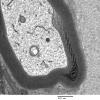

PERIPHERAL NEUROPATHY

3 NORMAL MYELIN & SCHWANN CELLS

3 Schmidt-Lanterman Clefts (2)